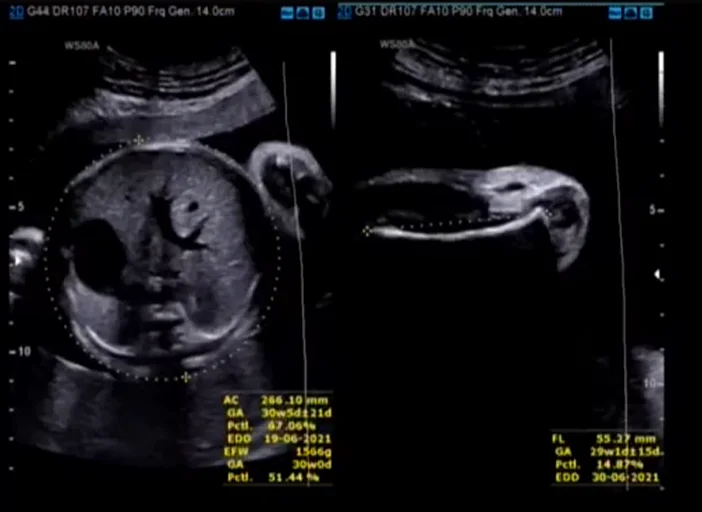

Loạn sản trung mô bánh nhau (Placental Mesenchymal Dysplasia - PMD)